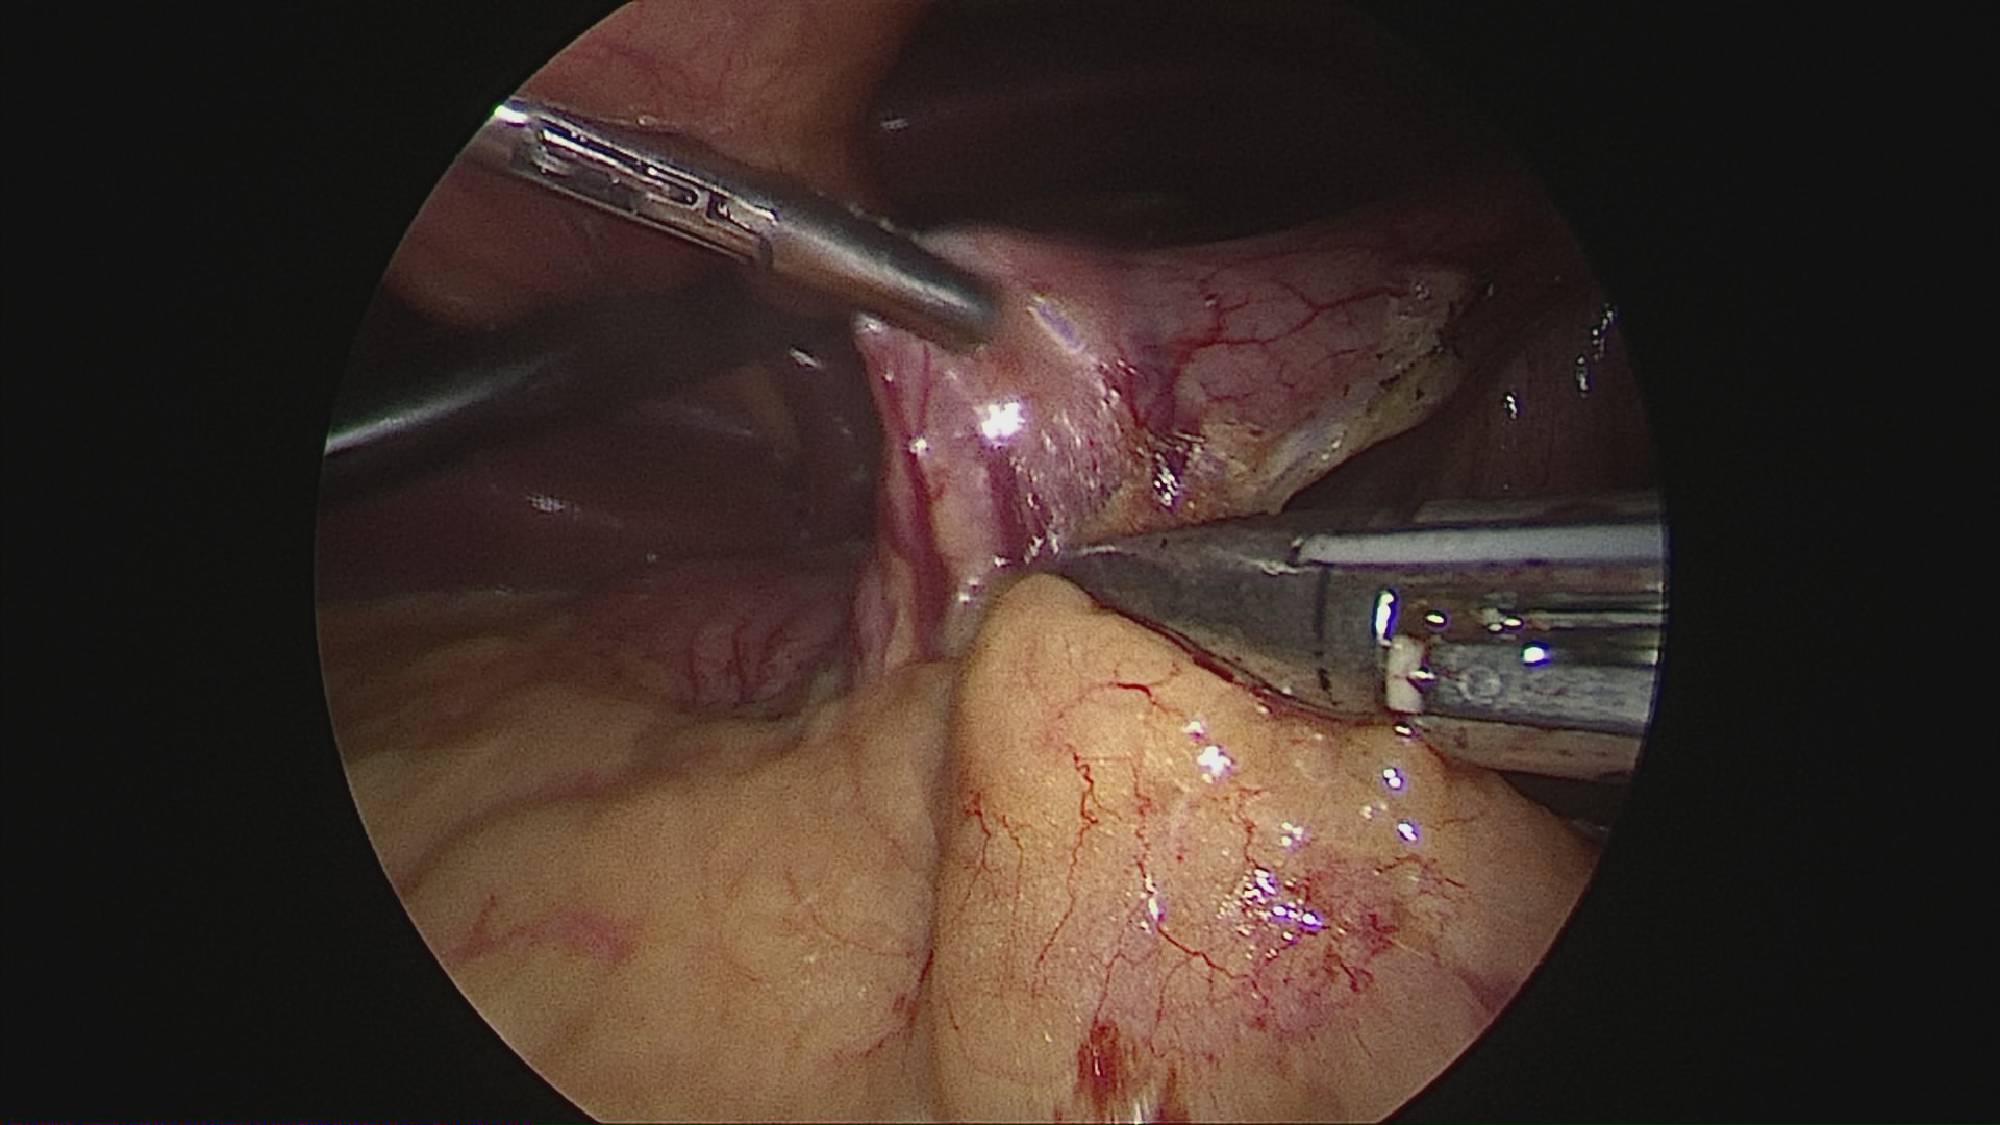

Gastrectomia longitudinală (gastric sleeve) este o intervenție care produce scăderea în greutate prin două mecanisme: restrictiv (îndepărtează o mare parte din stomac lăsând un rezervor de 80-120 ml) și hormonal (prin extirparea fundului gastric se reduce semnificativ secreția hormonului foamei, grelina).

Operația ”de micșorare a stomacului” se realizează miniminvaziv (laparoscopic) și constă în îndepărtarea marii curburi gastrice cu păstrarea antrului gastric și a micii curburi sub forma unui tub calibrat pe o sondă.